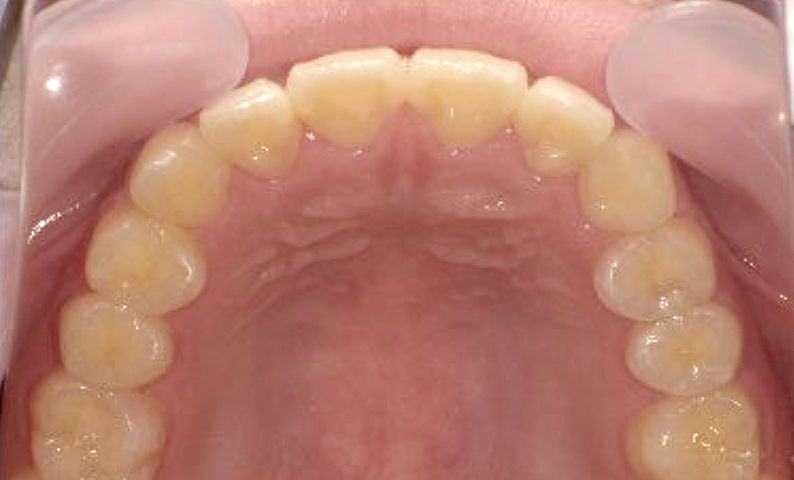

症例_001 上顎だけの部分矯正

治療期間:7ヶ月金額:30万円+税女性出っ歯上の前歯だけ

| Before | After |